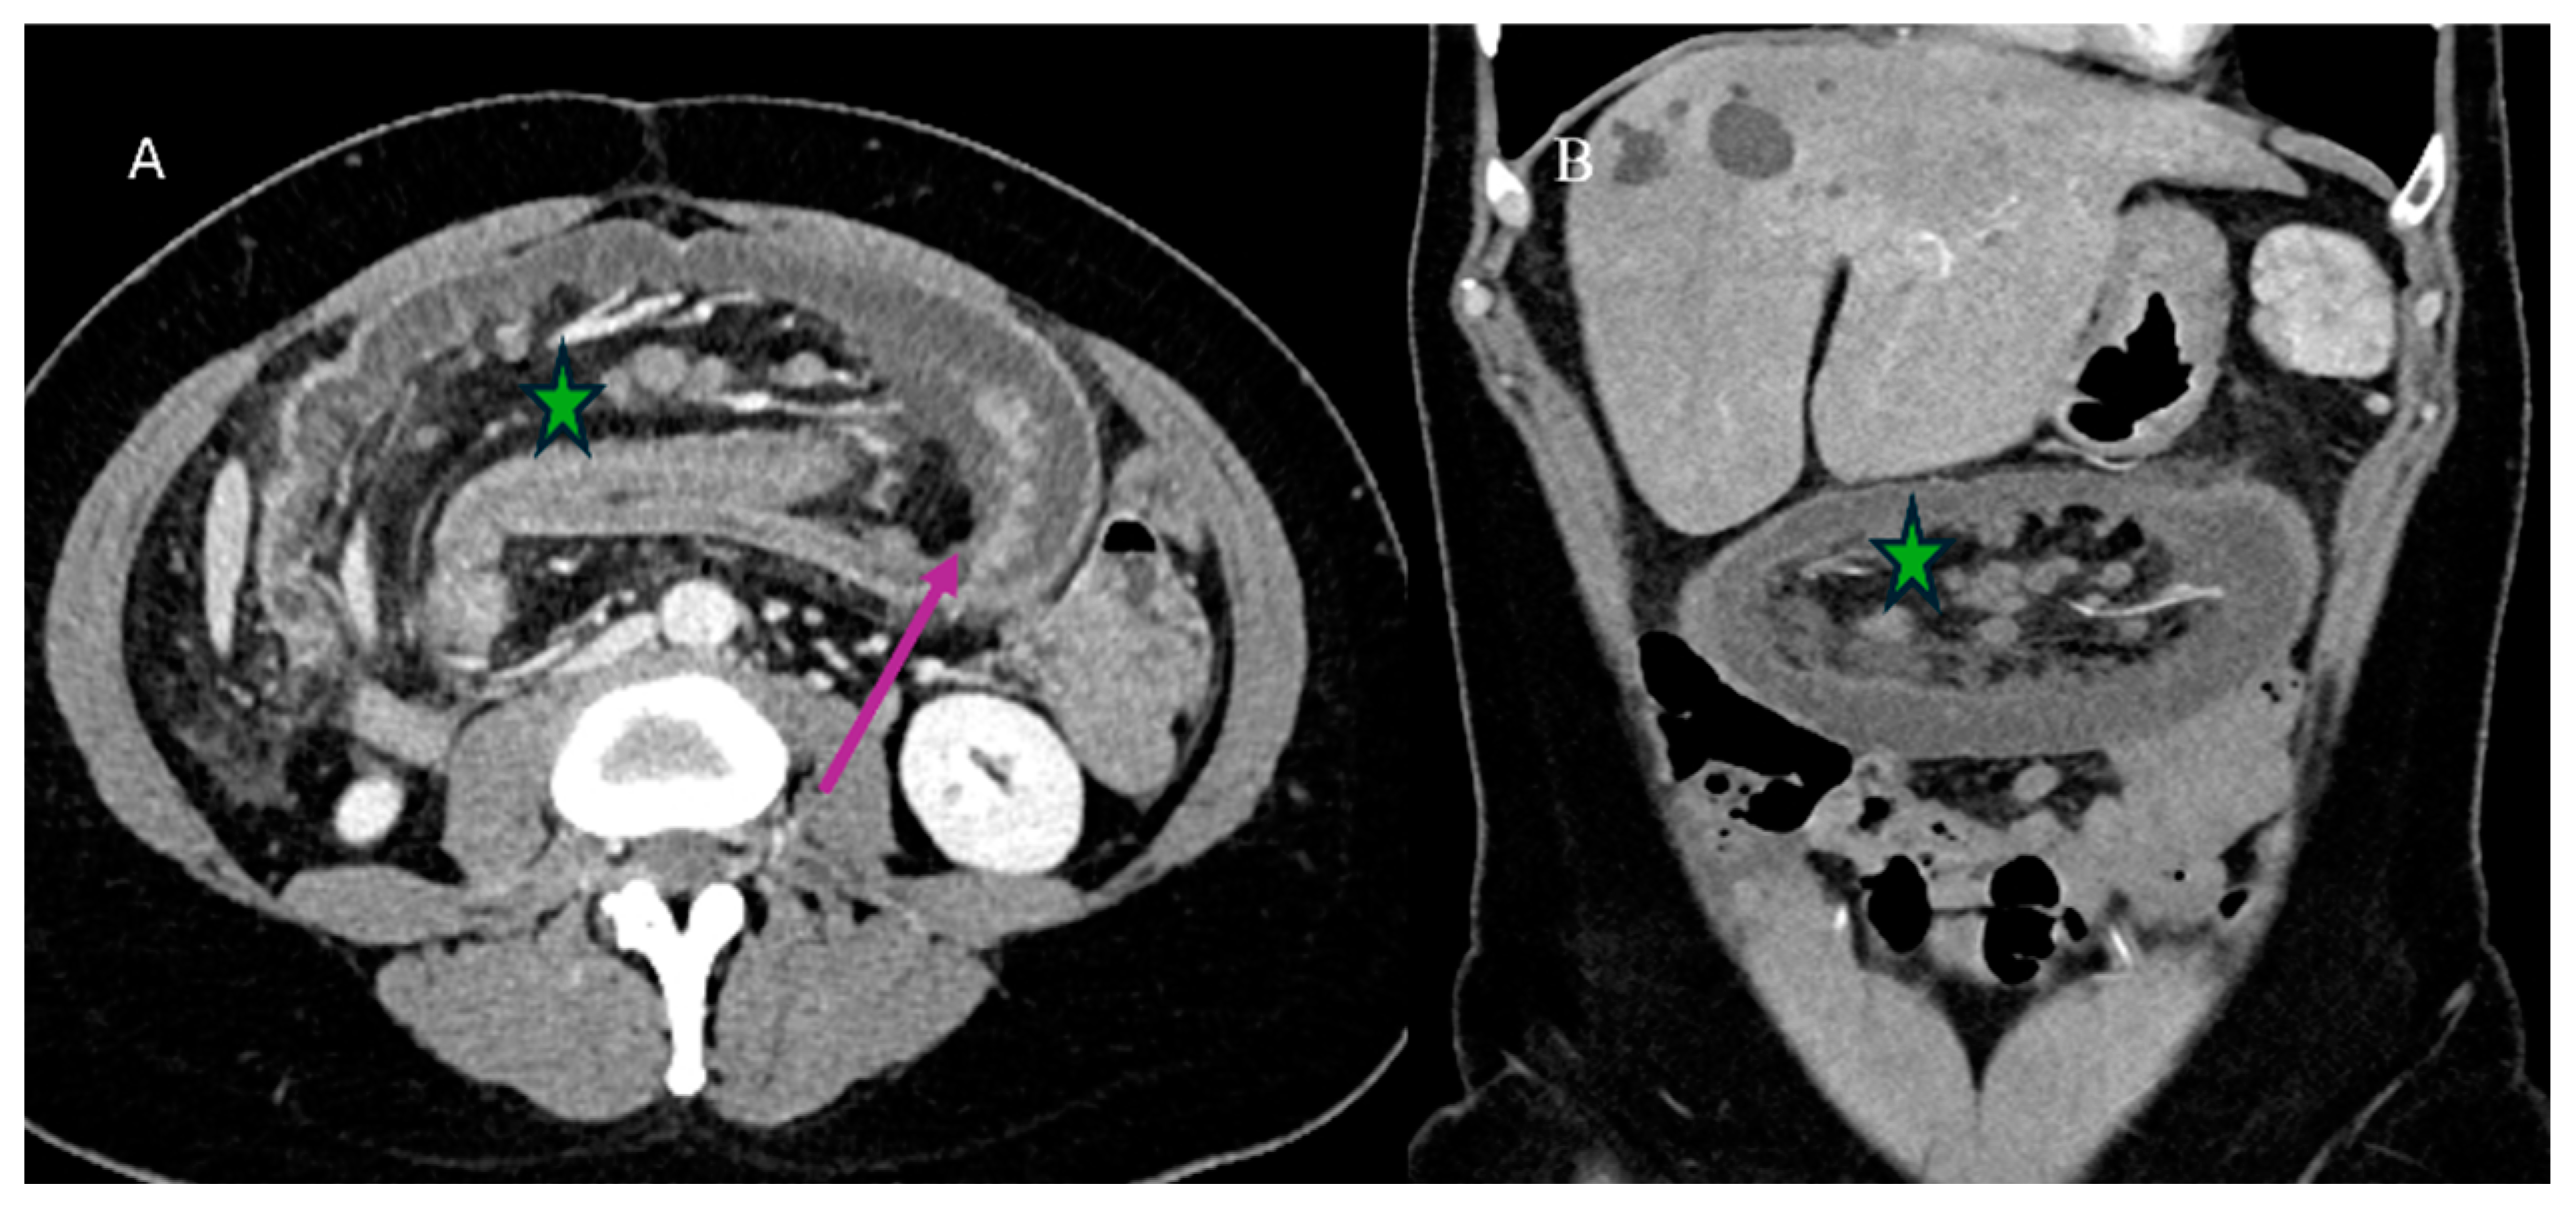

- Tuca, A.; Guell, E.; Martinez-Losada, E.; Codorniu, N. Malignant bowel obstruction in advanced cancer patients: Epidemiology, management, and factors influencing spontaneous resolution. Cancer Manag. Res. 2012, 4, 159–169. [Google Scholar] [CrossRef]

- Alshamsan, B.; Aseafan, M.; Badran, A.; Shaheen, A.; Elshenawy, M.A.; Bazarbashi, S.; Aljubran, A.H. Characteristics and outcomes of small bowel adenocarcinoma: 14 years of experience at a single tertiary hospital in Saudi Arabia. Mol. Clin. Oncol. 2023, 18, 17. [Google Scholar] [CrossRef]

- Kroepfl, V.; Bellotti, R.; Gasser, E.; Esswein, K.; Esser, H.; Kafka-Ritsch, R.; Öfner, D.; Perathoner, A. Small bowel neuroendocrine tumors: An analysis of clinical presentation, diagnostic workup and surgical approach—A single center retrospective study. Front. Surg. 2023, 10, 1072435. [Google Scholar] [CrossRef]

- Basendowah, M.H.; Ashour, M.A.; Hassan, A.Y.; Alshaynawi, S.; Alyazidi, L.K. Multiple small intestinal neuroendocrine tumors with findings of intestinal obstruction. Cureus 2021, 13, e17629. [Google Scholar] [CrossRef] [PubMed]

- Behi, H.; Omry, A.; Dallagi, R.; Changuel, A.; Troudi, D.; Khalifa, M.B. Diagnosing and managing small bowel neuroendocrine tumors presenting as acute obstruction in an elderly patient: A case report and comprehensive management overview. Int. J. Surg. Case Rep. 2024, 122, 110126. [Google Scholar] [CrossRef]